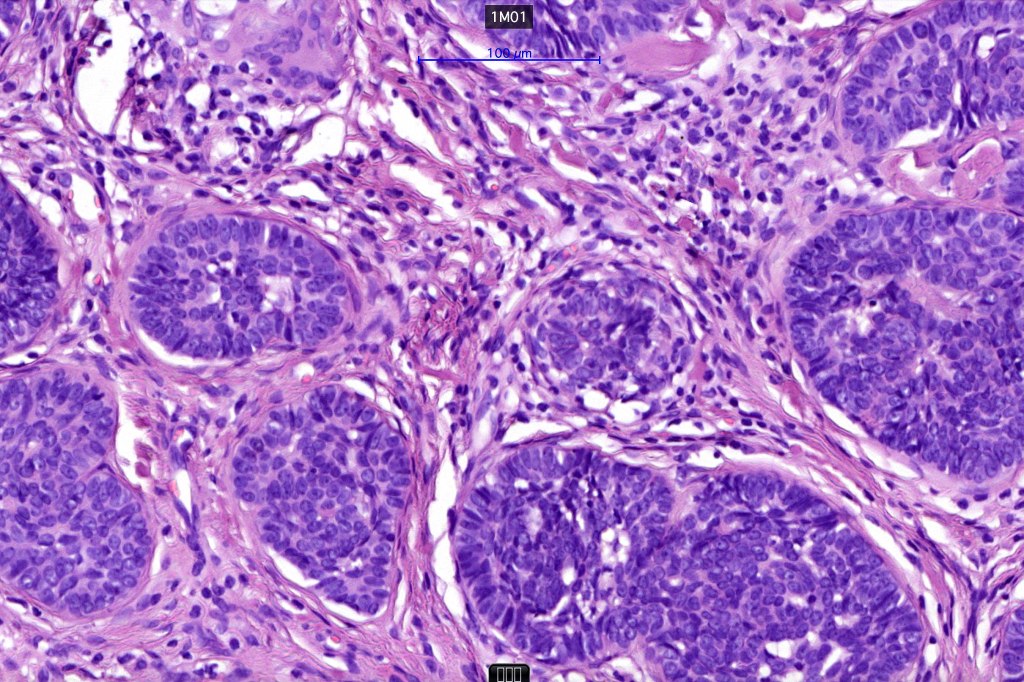

•Basaloid lobules show peripheral palisading

•Perifollicular mesenchyme is always conspicuous and sometimes densely aggregated are seen indenting the baslaloid lobules (papillary mesenchymal bodies)

•Narrow epithelial strands arising from the basaloid lobules are often present

Trichoepithelioma should be distinguished from trichoblastoma since the latter is very rarely syndromic. Trichoepithelioma is largely a dermal tumor whereas trichoblastoma often extends from the dermis into subcutaneous fat or deeper in very large examples. Papillary mesenchymal bodies are much better formed and generally more obvious in trichoepithelioma. Trichoepithelioma must also be distinguished from basal cell carcinoma. Retraction artifact & stromal mucin are features of basal cell carcinoma and not trichoepithelioma. Papillary mesenchymal bodies are not seen in basal cell carcinoma.